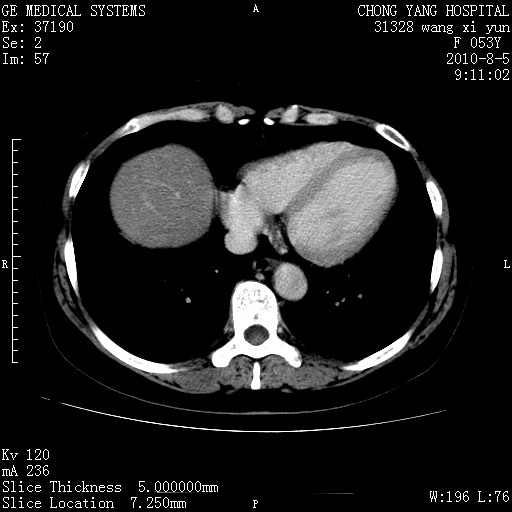

标题: CT28214:F41Y 血尿二十天,建议盆腔平扫加增强。

1)考虑肝左叶胆管细胞癌。2)脂肪肝。